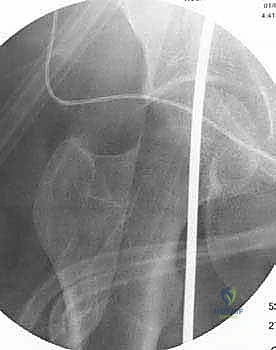

تُعد الأشعة السينية (X-rays) الممتدة من الحوض إلى الكاحل (Scanogram) ضرورية جداً لحساب زاوية التقوس بدقة وتحديد مقدار التعديل المطلوب جراحياً.

قبل العملية، يتم قياس زوايا الركبة بدقة متناهية. كل درجة من درجات التعديل يتم حسابها مسبقاً.

استخدام التخطيط الرقمي يضمن عدم حدوث تصحيح مفرط (Over-correction) أو تصحيح ناقص (Under-correction)، وهو ما يميز الجراح الخبير عن غيره.